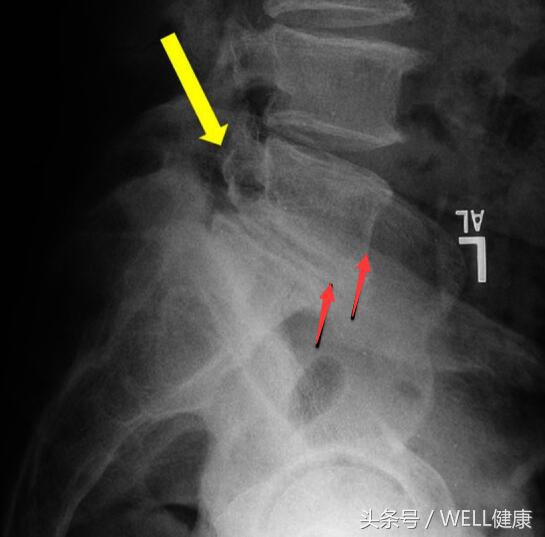

红箭头处为腰椎滑脱